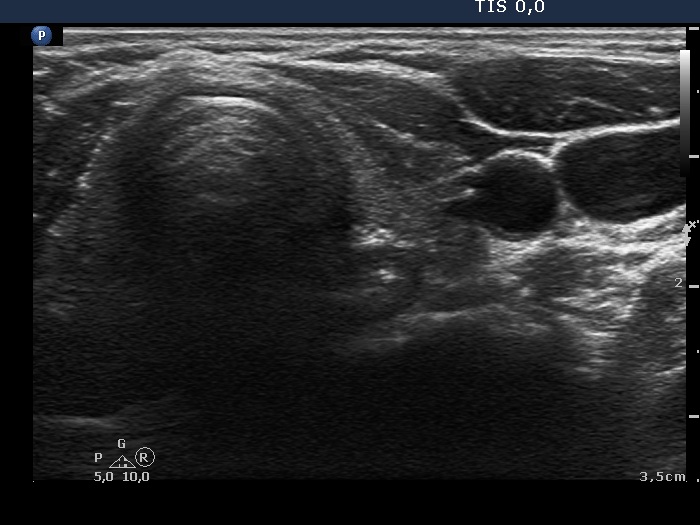

Follow-up examination 3 years later (second row of images):

Ultrasonography: The thyroid was unchanged. The lesions in the dorsal part of the right lobe increased in size and a small hypoechogenic area appeared in the ventral part of the left lobe.

Scintigraphy disclosed parathyroid enlargement not only in the right but even in the left side.

Surgery was performed. Histopathology disclosed hyperplasia of all four parathyroids.